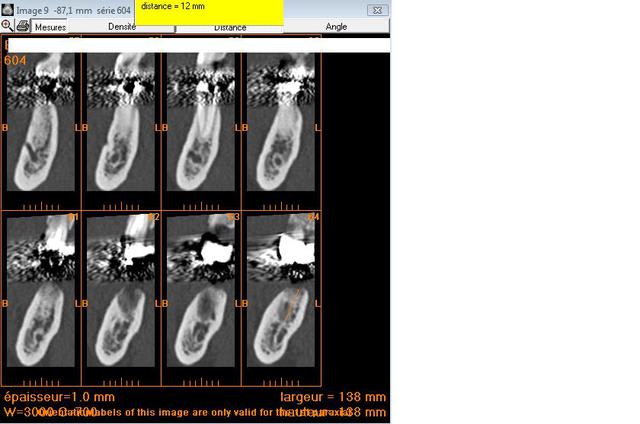

Deux implants en 36 46 et j'espere vous avoir donné les bonnes coupes sinon cela veut dire que je n'ai rien compris !!!

j' ai fais des mesures avec le logiciel pour un implant de 12 mm

sur les bonnes coupes je l'espere ;)

Pour le diametre : 4 ou 5 ?